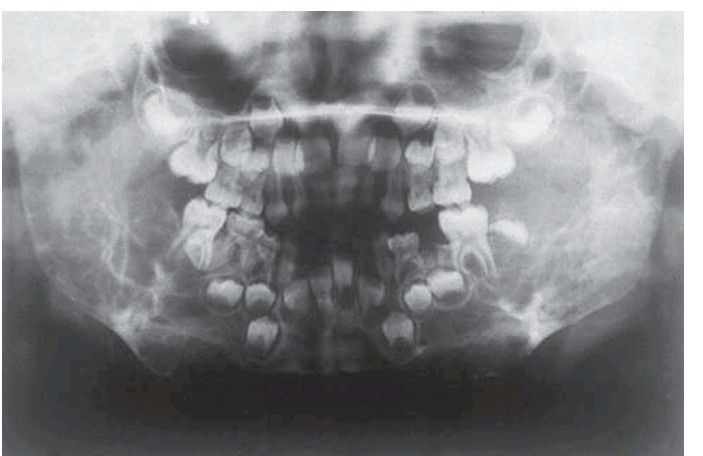

Cherubism

. Both rami, much of the body of the mandible and the posterior maxillae are expanded by multilocular radiolucent lesions which have displaced and destroyed developing teeth.